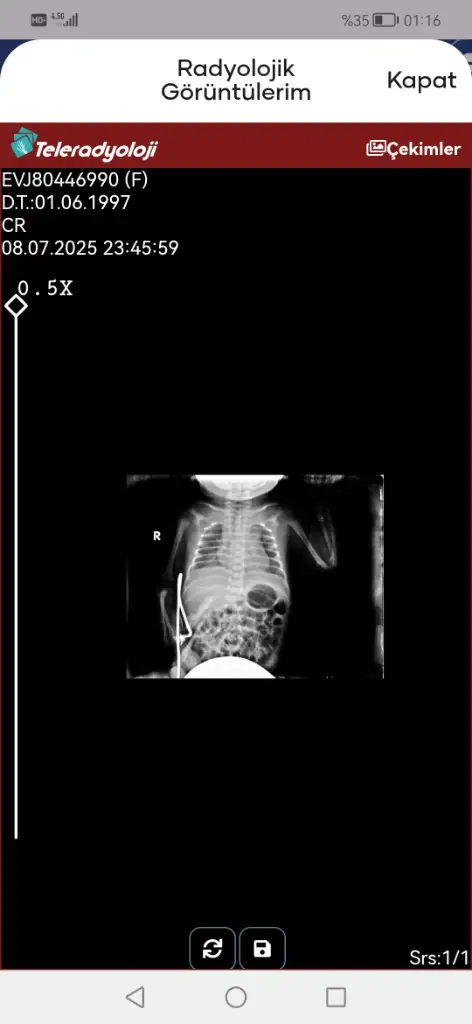

Evet entübasyon hortumu görünmüyor iki hortum olmalıydı ağzında. Entübeden ayrılması da iyi bir şey süt de azıcık gaz yapmış hatta bebişe. Süt aldıkça bu değerler toparlanır. Kan gazına göre bebeğiniz solunumu tölere edebiliyor diyebiliriz bunlar güzel haberler

• Screenshot_20250709_011620_tr.gov.saglik.enabiz.webp

Screenshot_20250709_011620_tr.gov.saglik.enabiz.webp

14,3 KB · Görüntüleme: 14